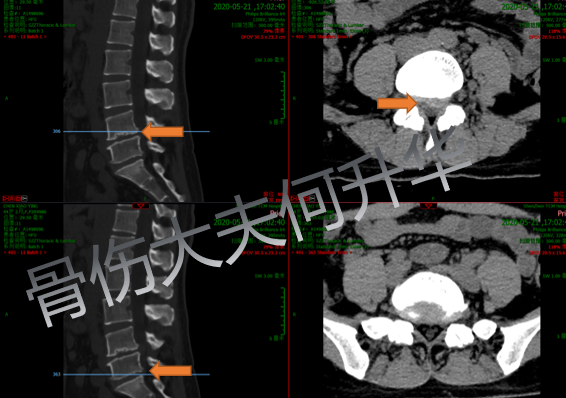

入院后,CT横断面片显示腰部左侧4/5

椎间盘突出症、腰椎4型椎体终板炎症表现